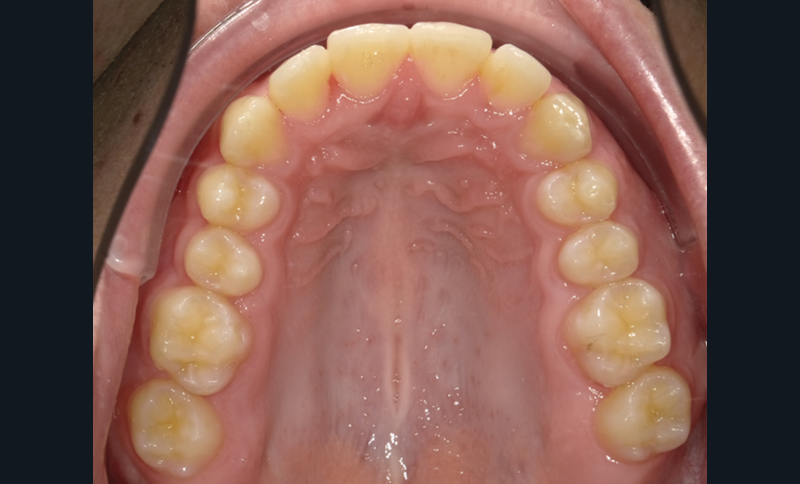

Le début et milieu d’après-midi seront consacrés à l’empreinte numérique, désormais utilisée pour les empreintes d’étude, les set-up, le thermoformage. Les Drs Guillaume Lecocq et Stéphane Desplanques monteront le thermoformage et comment ces empreintes numériques peuvent permettre de confectionner des appareils vestibulaires, linguaux, voire des aligneurs (fig. 1 et 2).